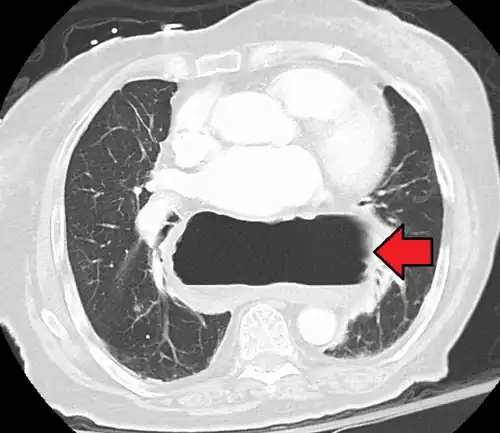

The diagnosis of a hiatal hernia is typically made through an upper GI series, endoscopy, high resolution manometry, esophageal pH monitoring, and computed tomography (CT). Barium swallow, as in the upper GI series, allows the size, location, stricture, and stenosis of oesophagus to be seen. It can also evaluate the oesophageal movements. Endoscopy can analyse the esophageal internal surface for erosions, ulcers, and tumours.

Meanwhile, manometry can determine the integrity of esophageal movements and the presence of esophageal achalasia. pH testing allows the quantitative analysis of acid reflux episodes. A CT scan is useful in diagnosing complications of hiatal hernia, such as gastric volvulus, perforation, pneumoperitoneum, and pneumomediastinum.[8]